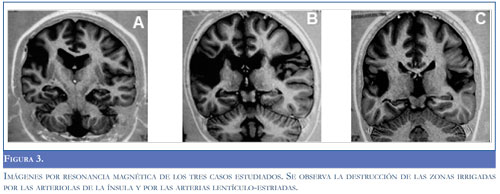

En las imágenes por resonancia magnética de los tres casos estudiados (Figura 3) observamos la destrucción de las zonas irrigadas por las arteriolas de la ínsula y por las arterias lentículo-estriadas. En uno de los casos (Figura 3A) hubo destrucción bilateral de la corteza de la ínsula y del opérculo frontal derecho; en los otros casos (Figuras 3B y 3C) las lesiones fueron más extensas; en el último caso (Figura 3C) hubo destrucción de los núcleos lenticulares y en el caso de la Figura 3B la lesión avanzó hasta el centro oval del lóbulo frontal derecho comunicada con el ventrículo lateral, lo que constituyó una verdadera esquizocefalia. Es de anotar que en ninguno de los casos hubo compromiso del lóbulo temporal, lo que concuerda con el plan de irrigación descrito.